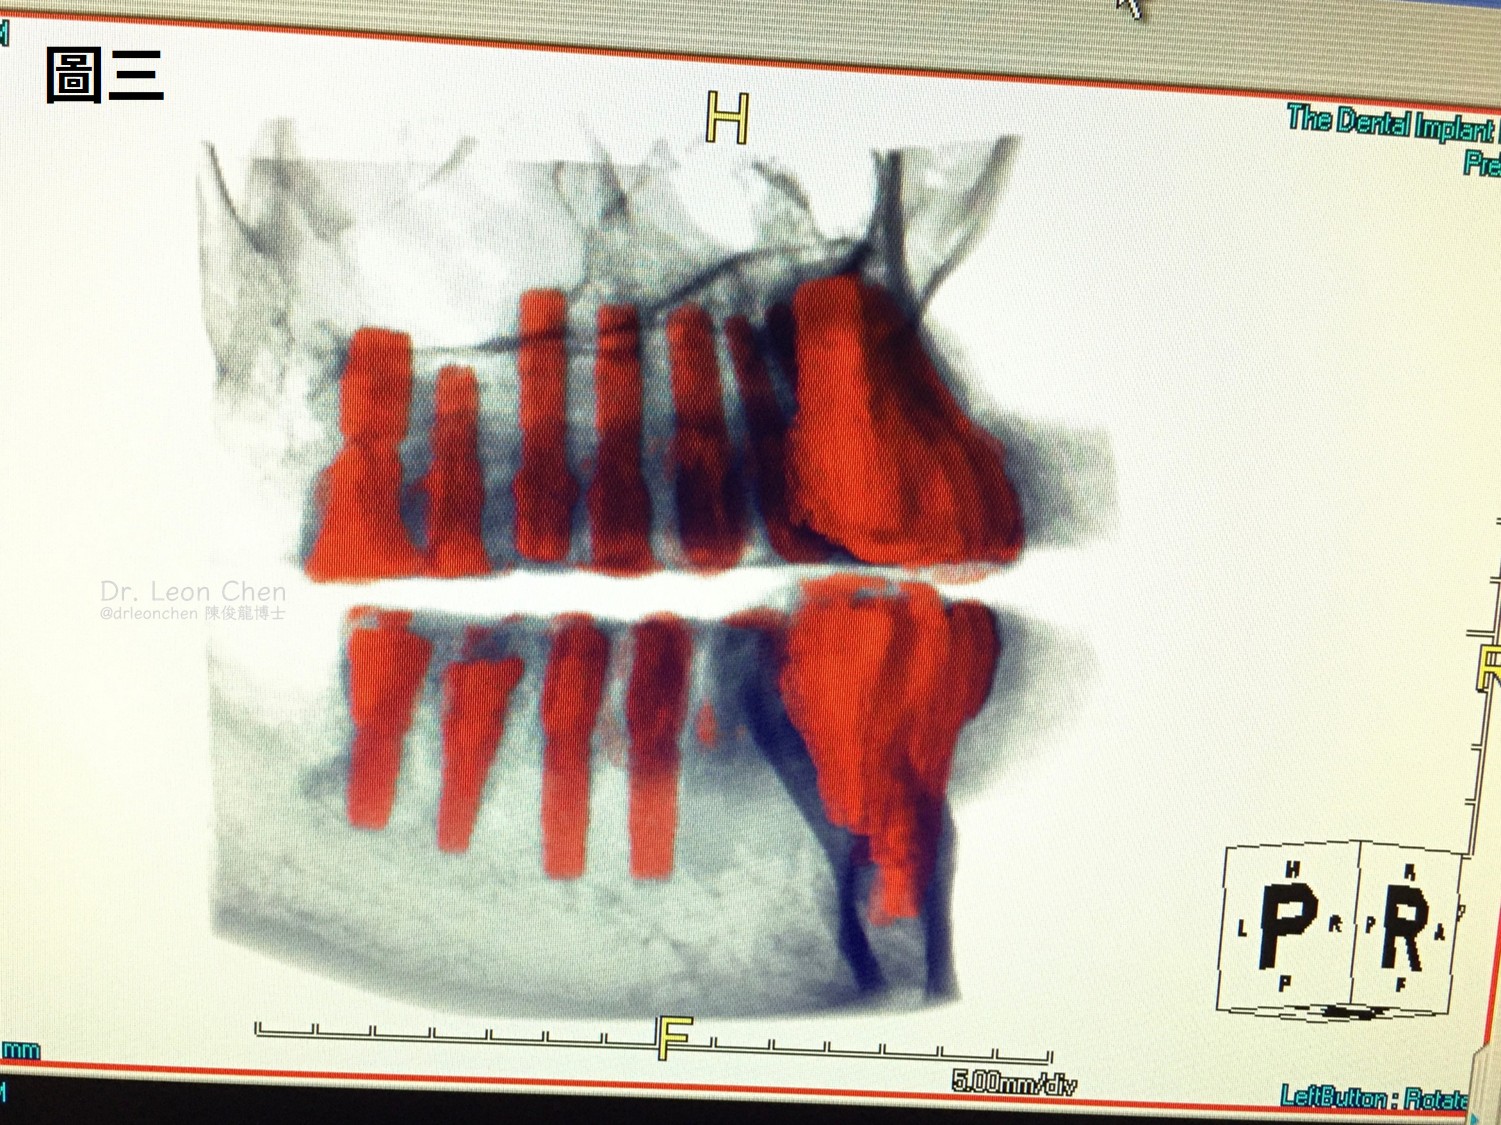

陳博士為患者拍了一張斷層掃描(圖一),特別強調的就是「植體角度」。

陳博士還分享其他二個全口28顆植牙案例(圖二~圖四),重點都在「角度」。

這些都是17年以上的老病人,持續追蹤、每一顆植牙都穩穩耐用。